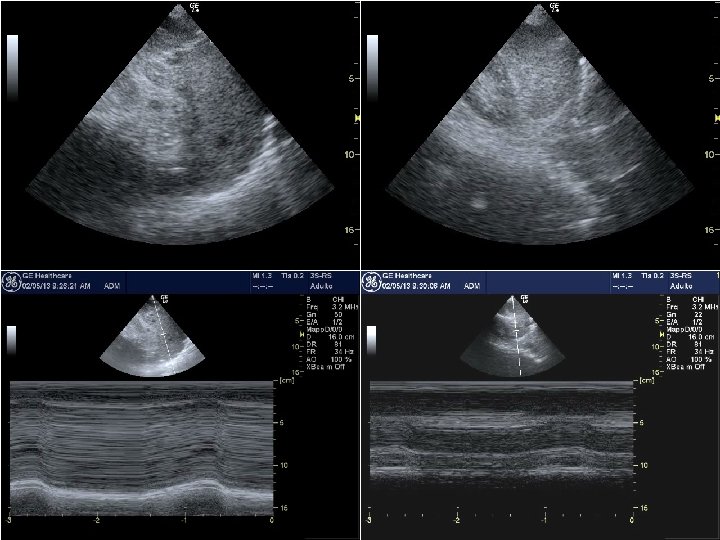

ECO SEPSI LA FUNZIONE SISTOLICA C • Nei modelli sperimentali di sepsi si può misurare la funzione contrattile ventricolare intrinseca (d. P/d. T), con riscontro costante di compromissione • La FE, impiegata in vivo come misura della funzione sistolica, è carico-dipendente in modo critico • La FE del VS è ridotta in una proporzione variabile dei pazienti con sepsi grave o shock settico, proporzione che aumenta progressivamente nelle prime 72 ore, con ritorno alla normalità entro 7 -10 gg • Nei pazienti che muoiono spesso la FE resta normale • La FE nei pazienti settici può essere considerata un indice inverso del postcarico oltre (e forse più) che un parametro della funzione sistolica del VS

ECO SEPSI LA FUNZIONE DIASTOLICA C • La disfunzione diastolica nei pazienti settici, valutata con il Doppler tissutale, è più frequente della disfunzione sistolica (circa 50% vs 30%) • La disfunzione diastolica è associata ad aumento di mortalità (RR quasi doppio rispetto ai pazienti che non presentano disfunzione diastolica), a differenza della disfunzione sistolica che non dimostra associazioni significative • La disfunzione diastolica ha un impatto negativo sul riempimento del VS, che diventa progressivamente dipendente dal precarico e dal mantenimento del RS con normofrequenza, condizioni spesso assenti nella sepsi

PROTOCOLLO FOCUS • Valutazione VCI: variazione respiratoria <15% vs >15% • Valutazione ispettiva funzione sistolica VS: normale (FE >45%), ridotta moderatamente (FE 30 -45%) o gravemente (FE <30%) • Valutazione disfunzione VD (VD ≥ VS, setto dislocato a sn) • Ricerca versamento pericardico e valvulopatie VALUTAZIONI ∆ VCI FE VS < 15% N > 15% < 45% < 15% < 45% INTERVENTI Fluidi DOBU STOP NO 20 -40 ml/Kg NO 10 -20 ml/Kg 5 g/Kg/m’ RIDUZIONE 5 g/Kg/m’

ECOMONITOR PRE-CARICO e POST-CARICO C • La VCI può essere monitorizzata per valutare il precarico dx e la risposta alla somministrazione di fluidi: quando l’indice di collassabilità risulti superiore al 40% vi è potenziale indicazione ad ulteriore carico volemico • Un indice monitorizzabile per il volume TD del VS è il diametro trasverso della cavità, indicativo di precarico ridotto quando < 3. 5 -4 cm • Contestualmente alla valutazione seriata della VCI e del volume TD del VS è indicato il monitoraggio dell’impegno interstiziale polmonare, predittivo della tolleranza al carico volemico

ECOMONITOR FUNZIONE SISTOLICA C • Il monitoraggio della funzione sistolica del VD e del VS, dopo la valutazione iniziale, ha un significato quando si preveda una variazione significativa nell’evoluzione clinica, fatto molto frequente nella sepsi • Il parametro più utilizzato è la FE, peraltro strettamente dipendente dalle condizioni di carico, oltre che dalla funzione contrattile intrinseca • La FE del VS può essere monitorizzata anche come indice inverso del postcarico, con riduzione progressiva correlata al controllo adeguato della vasoplegia periferica

ECOMONITOR C Disfunzione VD

ECOMONITOR C Disfunzione VS